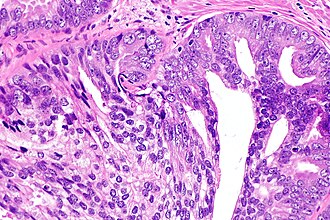

Intraductal carcinoma of prostate. H&E stain. | |

| LM | major criteria : glands 2x normal (peripheral zone) glands, basal cells present, "cytologically malignant cells" (nuclear hyperchromasia, nuclear enlargement, nucleoli), fills the lumen ("expansile") but does not have to be "solid", +/-comedonecrosis; minor criteria : branching of ducts at right angles, rounded/smooth gland outlines, two cell populations (malignant appearing at periphery of gland, benign appearing - centre of gland) |

Intraductal carcinoma of the prostate, abbreviated IDC-P, is a proliferation of malignant prostate cells within glands that have an intact basal cell layer.

Required major criteria:[6][7]

- Glands 2x normal (peripheral zone) glands.

- Basal cells present (proven by IHC).

- "Cytologically malignant cells" = nuclear hyperchromasia, nuclear enlargement, nucleoli.

- Fills the lumen ("expansile") but does not have to be "solid".

- Solid = no spaces between the cells.

Additional (major) criterion:[6]

- Comedonecrosis.

Minor criteria

Minor criteria:[6]

- Branching of ducts at right angles.

- Rounded/smooth gland outlines.

- Two cell populations:

- Malignant population (enlarged nuclei with hyperchromasia and nucleoli) = peripheral location in gland.

- Benign population (smaller nuclei, no nucleoli) = central location in gland.